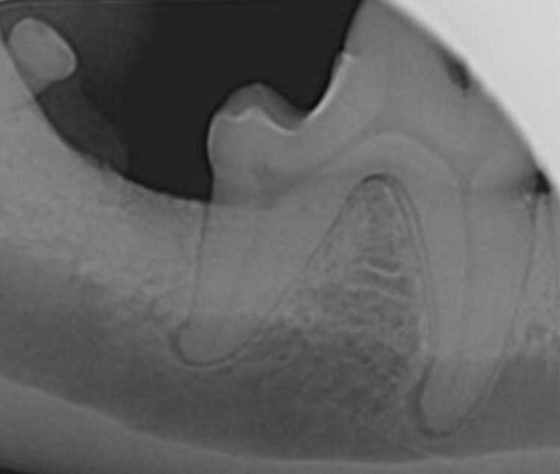

Figure 5. Repeat radiographs of the same patient as Figure 4, taken five months after periodontal therapy. The vertical bone defects have filled with new bone and periodontal ligament has redeveloped around the root, indicating successful treatment of periodontal disease. It should be noted a degree of horizontal bone loss is still evident, which is to be expected as alveolar bone height is known to be a more permanent change.